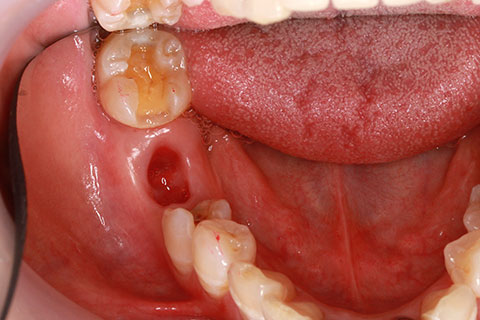

• 症例2

治療前

インプラント埋入時

治療後

年齢・性別

57歳男性

治療期間

3ヶ月

抜歯

なし

治療費

154万円

備考

左上5.6.7 及び左下6.7欠損

治療内容

左上5.6.7と左下6.7欠損部にインプラント埋入

施術の副作用(リスク)

オペによる知覚障害。インプラントによる歯肉炎。インプラント脱落。